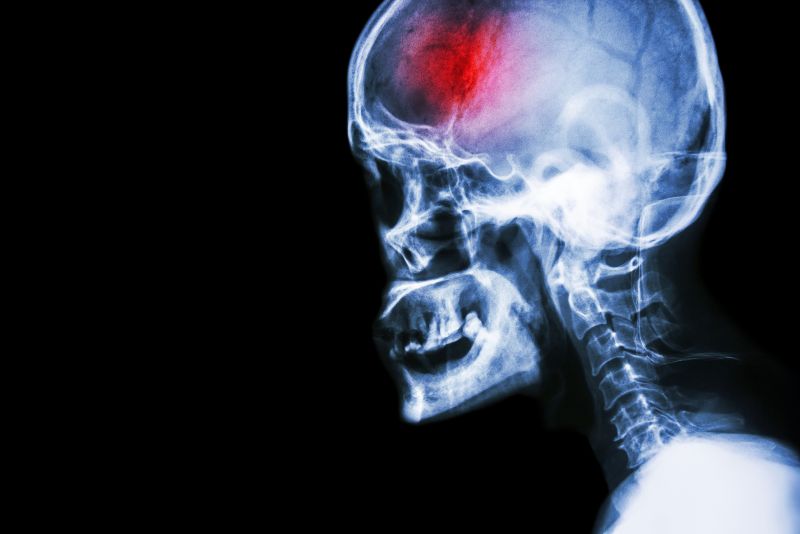

Head X-ray

Head X-rayA stroke is a serious medical emergency that requires immediate action in order to achieve the best eventual outcomes. Early medical intervention, as well as early, consistent and ongoing rehabilitation will positively affect your long term capabilities.  Physical therapy services at FYZICAL Nevada Missouri can assist you to recover from your stroke and regain your maximum potential.